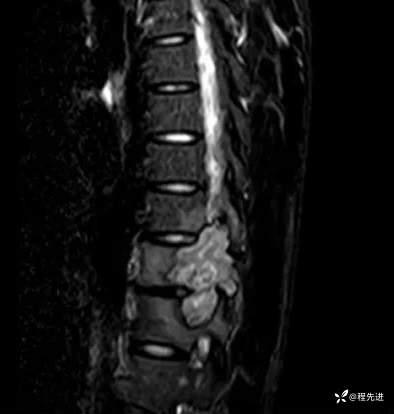

MR:

T 2压脂: